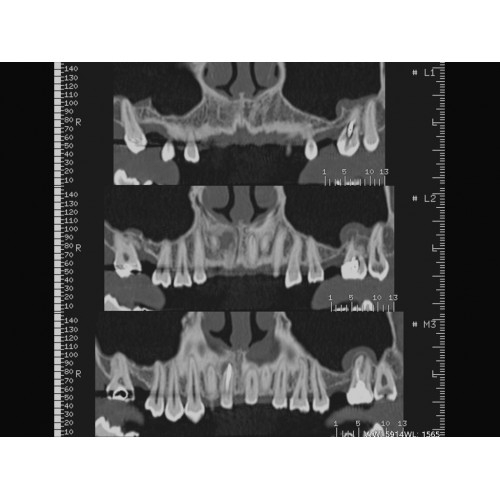

Неврологические исследования

• Выявление инсультов, опухолей головного мозга и травматических повреждений.

• Диагностика заболеваний позвоночника и межпозвоночных грыж.

• Диагностика сложных переломов и повреждений суставов.

• 3D-реконструкция костных структур для планирования операций.